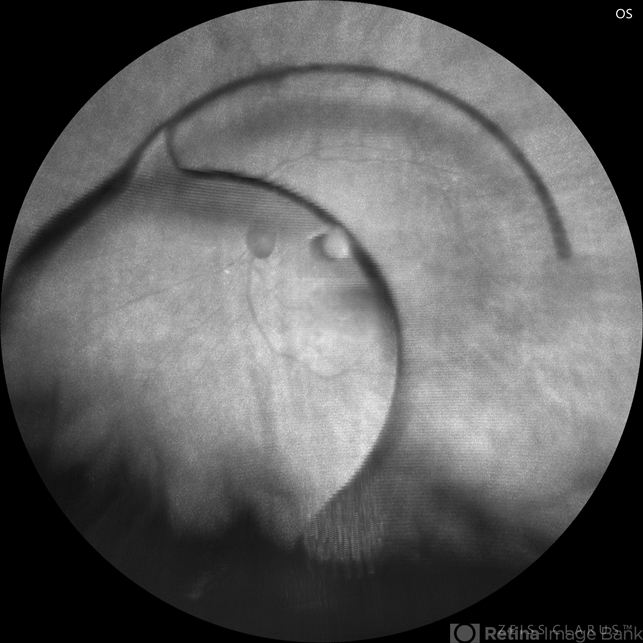

- dislocated posterior chamber intraocular lens (PCIOL)

- Traumatic dislocation of IOL in vitreous cavity .